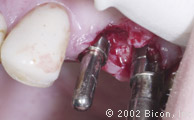

1. | 失败的三单位固定桥。 |